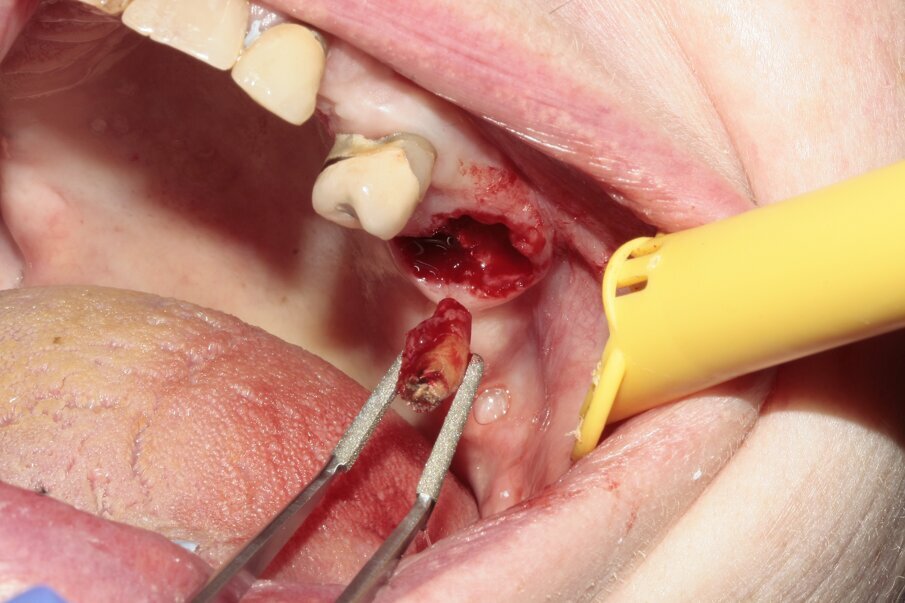

Fig. 9: The mesiobuccal root was removed.

Fig. 10: All roots were extracted separately.

The new, very thin Luxator P-series periotome made it possible to perform an atraumatic extraction with minimal loss of bone. Luxator P4, with its extremely sharp dual-edge blade, was used, followed by Luxator P1, once some space was created. Although the blades of these sophisticated instruments are reinforced with a titanium coating, they should only be used to cut the periodontal ligament and never to elevate the tooth. After sectioning the tooth and gently cutting the periodontal ligament, each root could easily be taken out with the help of diamond tweezers.